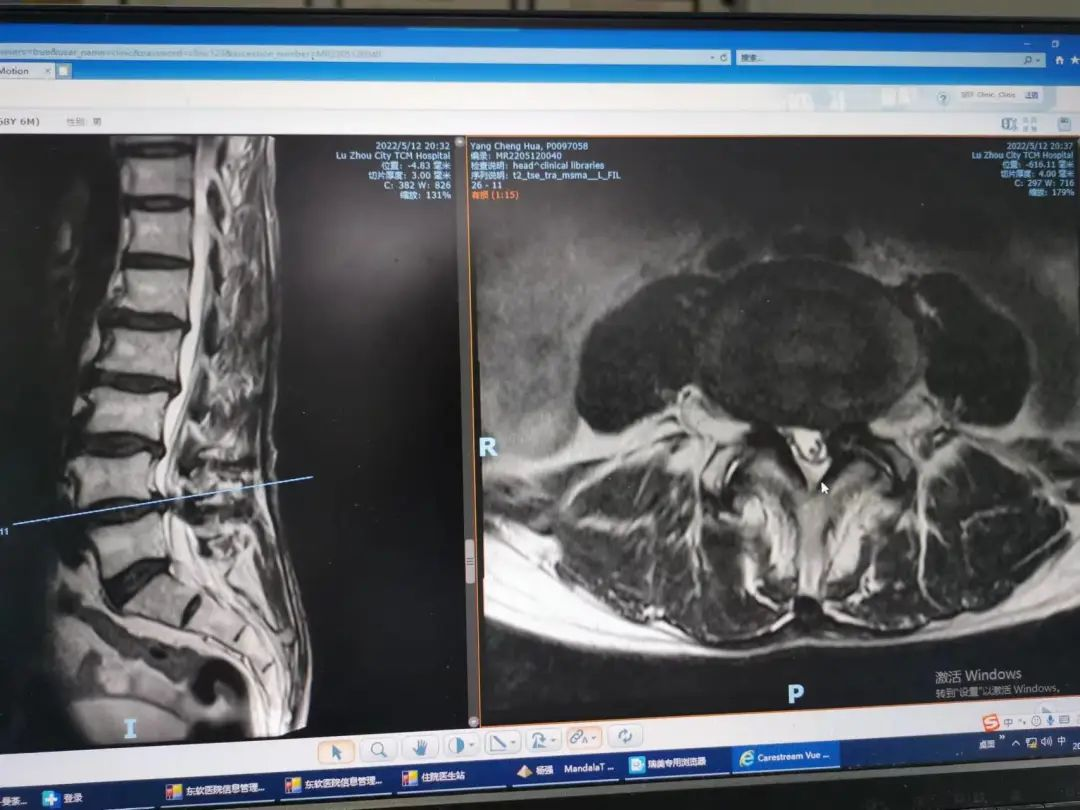

楊先生腰椎管狹窄癥拍片

楊先生脊髓性頸椎病拍片